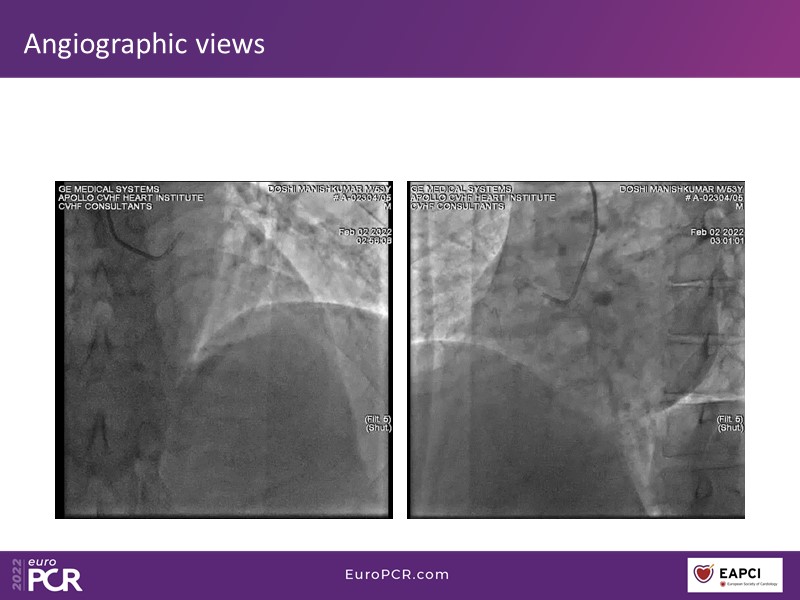

- To know why sirolimus coated balloon is the ideal choice in native vessel disease treatment through a case presentation